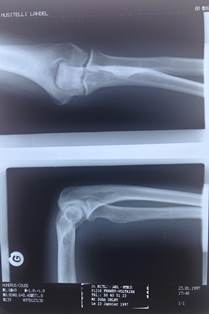

We are born with about 300 soft bones. During childhood and adolescence, the cartilage grows and is slowly replaced by hard bone. Some of these bones later fuse together, so that the adult skeleton has 206 bones.

We lose 94 bones along the way.

Until the x-ray, all knowledge of human anomalies (apart from visible ones) was limited to those found by anatomists at dissection. But now, new living anatomy was being shown on radiographs.

As this different view of the body came about, the interpretation of shadows had to be made with care. Early radiologists were like aircraft spotters.[ix] Abnormalities of forensic importance were (still are) often subtle and the shadows cast by the new rays could often be confusing. And, of course, what was normal?